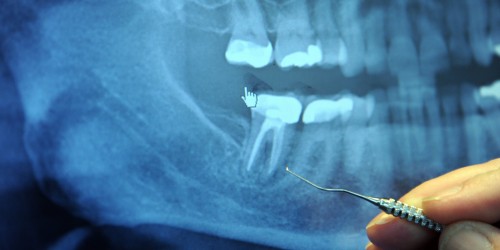

Root canal treatment is one of the areas that hold the most promise for the use of lasers in dentistry. A root canal involves locating all the canals present in the tooth, shaping them and enlarging them, disinfecting them and then finally filling them with a biocompatible material.

Lasers can help in the shaping and enlarging step but as mentioned earlier, they travel in straight lines, while a root canal is almost always curved in at least two dimensions. This means that their use is limited to a select few circumstances.

Disinfecting root canals is another matter, though. Several studies have found that disinfectants that are activated through lasers are very effective. Another technique that involves the use of acoustic waves being produced by lasers to disinfect the canals, called photodynamic therapy, has also shown very encouraging results in studies.

The only thing that dentists worry about is the increase in temperature that takes place with the use of lasers. This can be extremely detrimental to the tooth being treated, as well as the surrounding ligaments and gingival fibers.

Advances have been made to incorporate the use of low energy lasers which do not cause an increase in temperature. Once again the inherent property of lasers to leave behind a sterile field is very desirable in disinfecting the root canals.